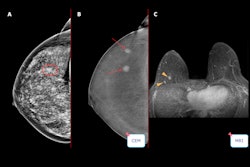

- Lunit Insight MMG: Mammography analysis solution

- Lunit Insight DBT: Digital breast tomosynthesis interpretation

The first commercial deployments are already underway, the firm added, including the use of Insight MMG at Radiologische Allianz in Hamburg, supporting the Hamburg breast cancer screening program under the Starvision network.

Together with deployments at Die Radiologie, a major regional hospital group operating over 20 medical sites across Bavaria, Lunit's software now supports approximately 120,000 breast cancer screenings and diagnoses annually across the two institutions, the company said.